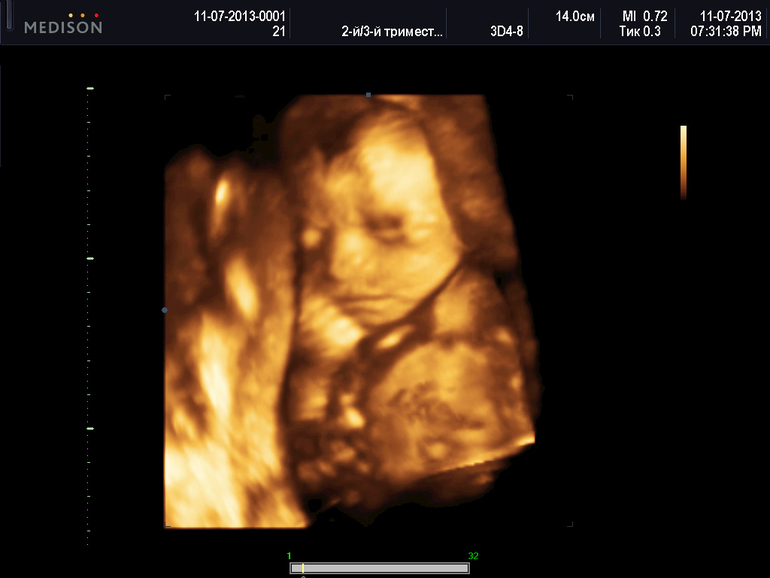

УЗИ, КТГ, доплерУраа!!!Сходили наконец-то на узи!!!!Все у нас супер!Все хорошо!!Мы перевернулись,теперь в головном предлежании.Плацента поднялась.По узи срок 22-23 недели,как и должно быть в принципе))Так же нам подтвердили мальчика,наделали видео три штуки,штук 10 фото на диске.Вообщем девочки я очень довольна.Единственное только думаю рано в 23 недели идти на 3D узи.Потому что малыш еще не до конца развился,ну зато такая память!!!Вообщем всем довольна!!!

Даже не знаю как еще отобразить свои эмоции!!!Малыш на узи сначала вел себя спокойно ручки к лицу прикладывал,будто задумался,потом стал головку прятать,не нравится нам показываться теперь((Ох как я жду этого пупса!!!!

Меня так удивило как он там лежит...ручки прикладывает к лицу.Руками дубасит меня оказывается,я думала у него ноги такие сильные,оказывается ручки.Так на папку похож..ИИИИй..милашка моя!!